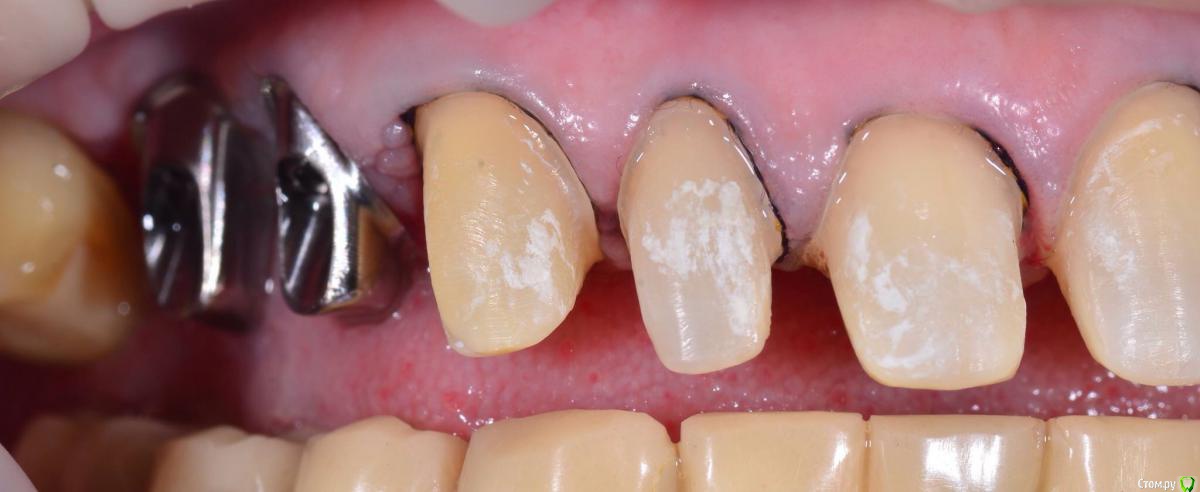

chervoncevdaniil Опубликовано 5 апреля, 2016 Поделиться Опубликовано 5 апреля, 2016 Обсуждали с пациентом что цвет шеек будет отличаться от блич коронок?Не был против? Ссылка на комментарий

togrul Опубликовано 5 апреля, 2016 Автор Поделиться Опубликовано 5 апреля, 2016 Конечно . Оставил для хорошей гигиены. Так как от хирургии отказалась. Ссылка на комментарий

Art 7 Опубликовано 5 апреля, 2016 Поделиться Опубликовано 5 апреля, 2016 Тогрул привет, так не оставляй, надо такие вещи либо закрывать десной либо керамикой. Керамика гигиеничнее чем оголеный корень 1 Ссылка на комментарий

togrul Опубликовано 5 апреля, 2016 Автор Поделиться Опубликовано 5 апреля, 2016 Тогрул привет, так не оставляй, надо такие вещи либо закрывать десной либо керамикой. Керамика гигиеничнее чем оголеный кореньПривет Артур. Посоветовавшис с пародонтологом решили оставить на границе ЭЦГ. И с точки зрения адгезивный фикцисации цемент зуба как я понимаю тяжело адгезивно подготовить. Спасибо . Ссылка на комментарий